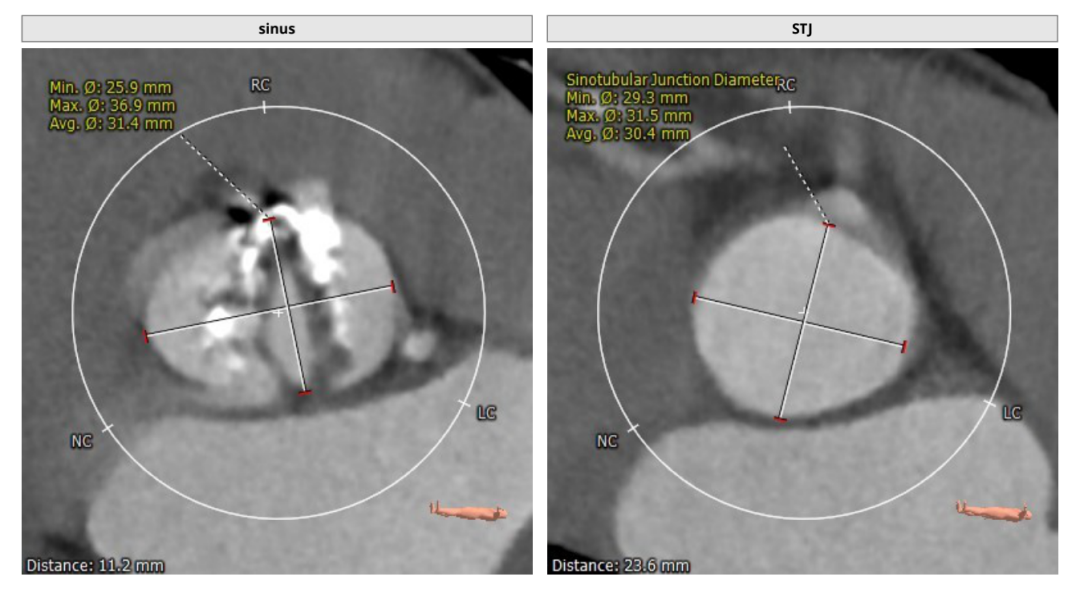

CT评估

瓣环直径:24.5mm,左室流出道直径:25.4mm

主动脉窦:25.9*36.9mm,STJ:30.4mm

升主动脉直径:36.5,心脏夹角:59度

左冠高度:20.1mm,右冠高度:19.5mm